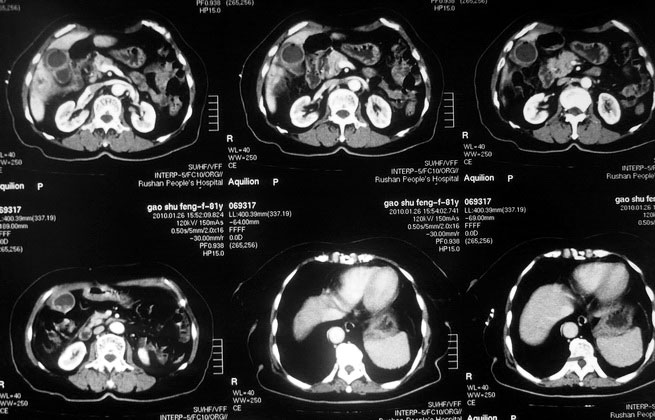

肝癌合并肝脓肿

女,80岁既往有胆系手术史。近2月出现食欲不振,近20天出现畏寒发热,体重约下降10kg,体温一般在38℃左右。血常规wbc正常,中性比例88%,cea 10.3,afp、ca199均正常。做过一次肝穿,抽出约3ml仿佛脓性液体。这是她的增强ct扫描,请大家帮帮忙。另外想问问肝脓肿和胆管细胞癌的ct表现有什么区别。谢谢了。

【湘江一滴】化脓性胆囊炎及胆管炎,肝内胆管积气、积液、扩张;胆囊壁增厚、强化;胆周积液。未见肝内占位征象。

【shuiyuan】化脓性胆囊炎及胆管炎,肝内胆管积气、积液、扩张;胆囊壁增厚、强化;胆周积液.

肝脓肿动脉期呈明显环形强化或蜂窝状强化,胆管细胞癌动脉期强化不明显,且伴肝内胆管扩张。

【zenxisengming 】肝内胆管扩张积气,胆囊比环形增厚,胆囊周围渗出,未见占位性病变,应该是胆道化脓性感染

【sunbin】肝内见多个气体密度影伴气液面,胆囊壁增厚,胆囊周围低密度环绕,未见强化,支持化脓性胆管炎、胆囊炎。

最近复查ct,做了第二次穿刺抽脓,顺便做了涂片病理活检,结果找到恶性肿瘤细胞,诊断肝癌合并肝脓肿。看来大家都走眼了啊。